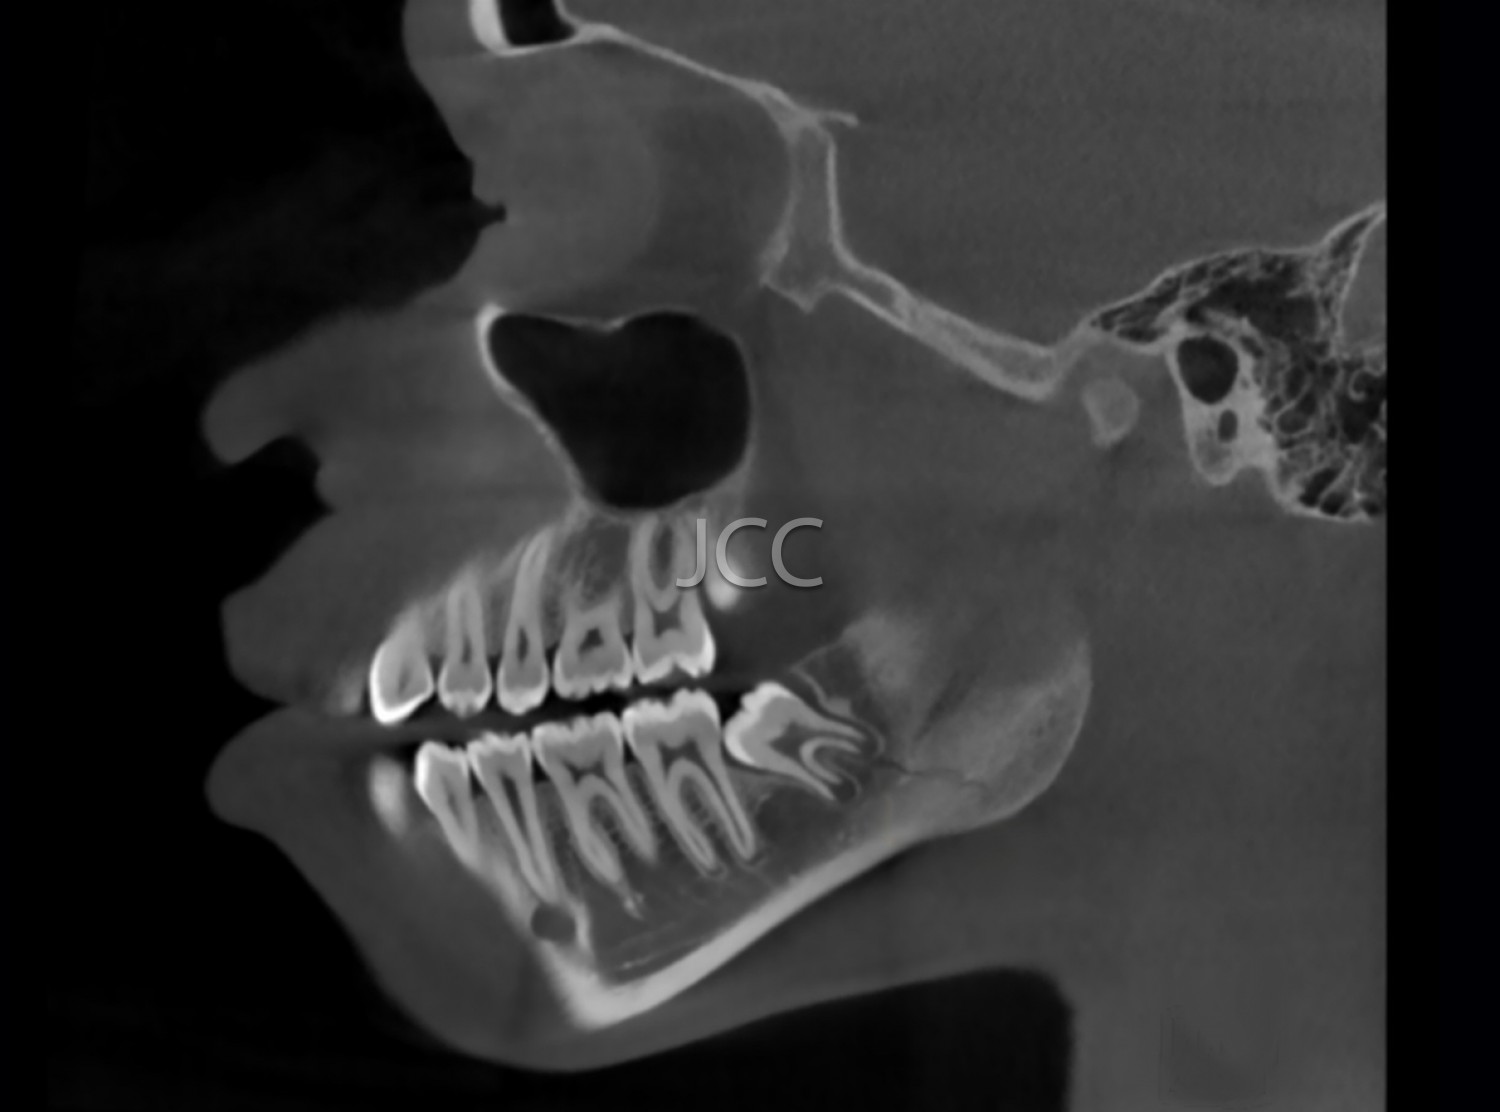

Dental Radiology - Maxillofacial CBCT / CT

Applications

• Orthognathic surgery

• Maxillofacial Surgery and Traumatology